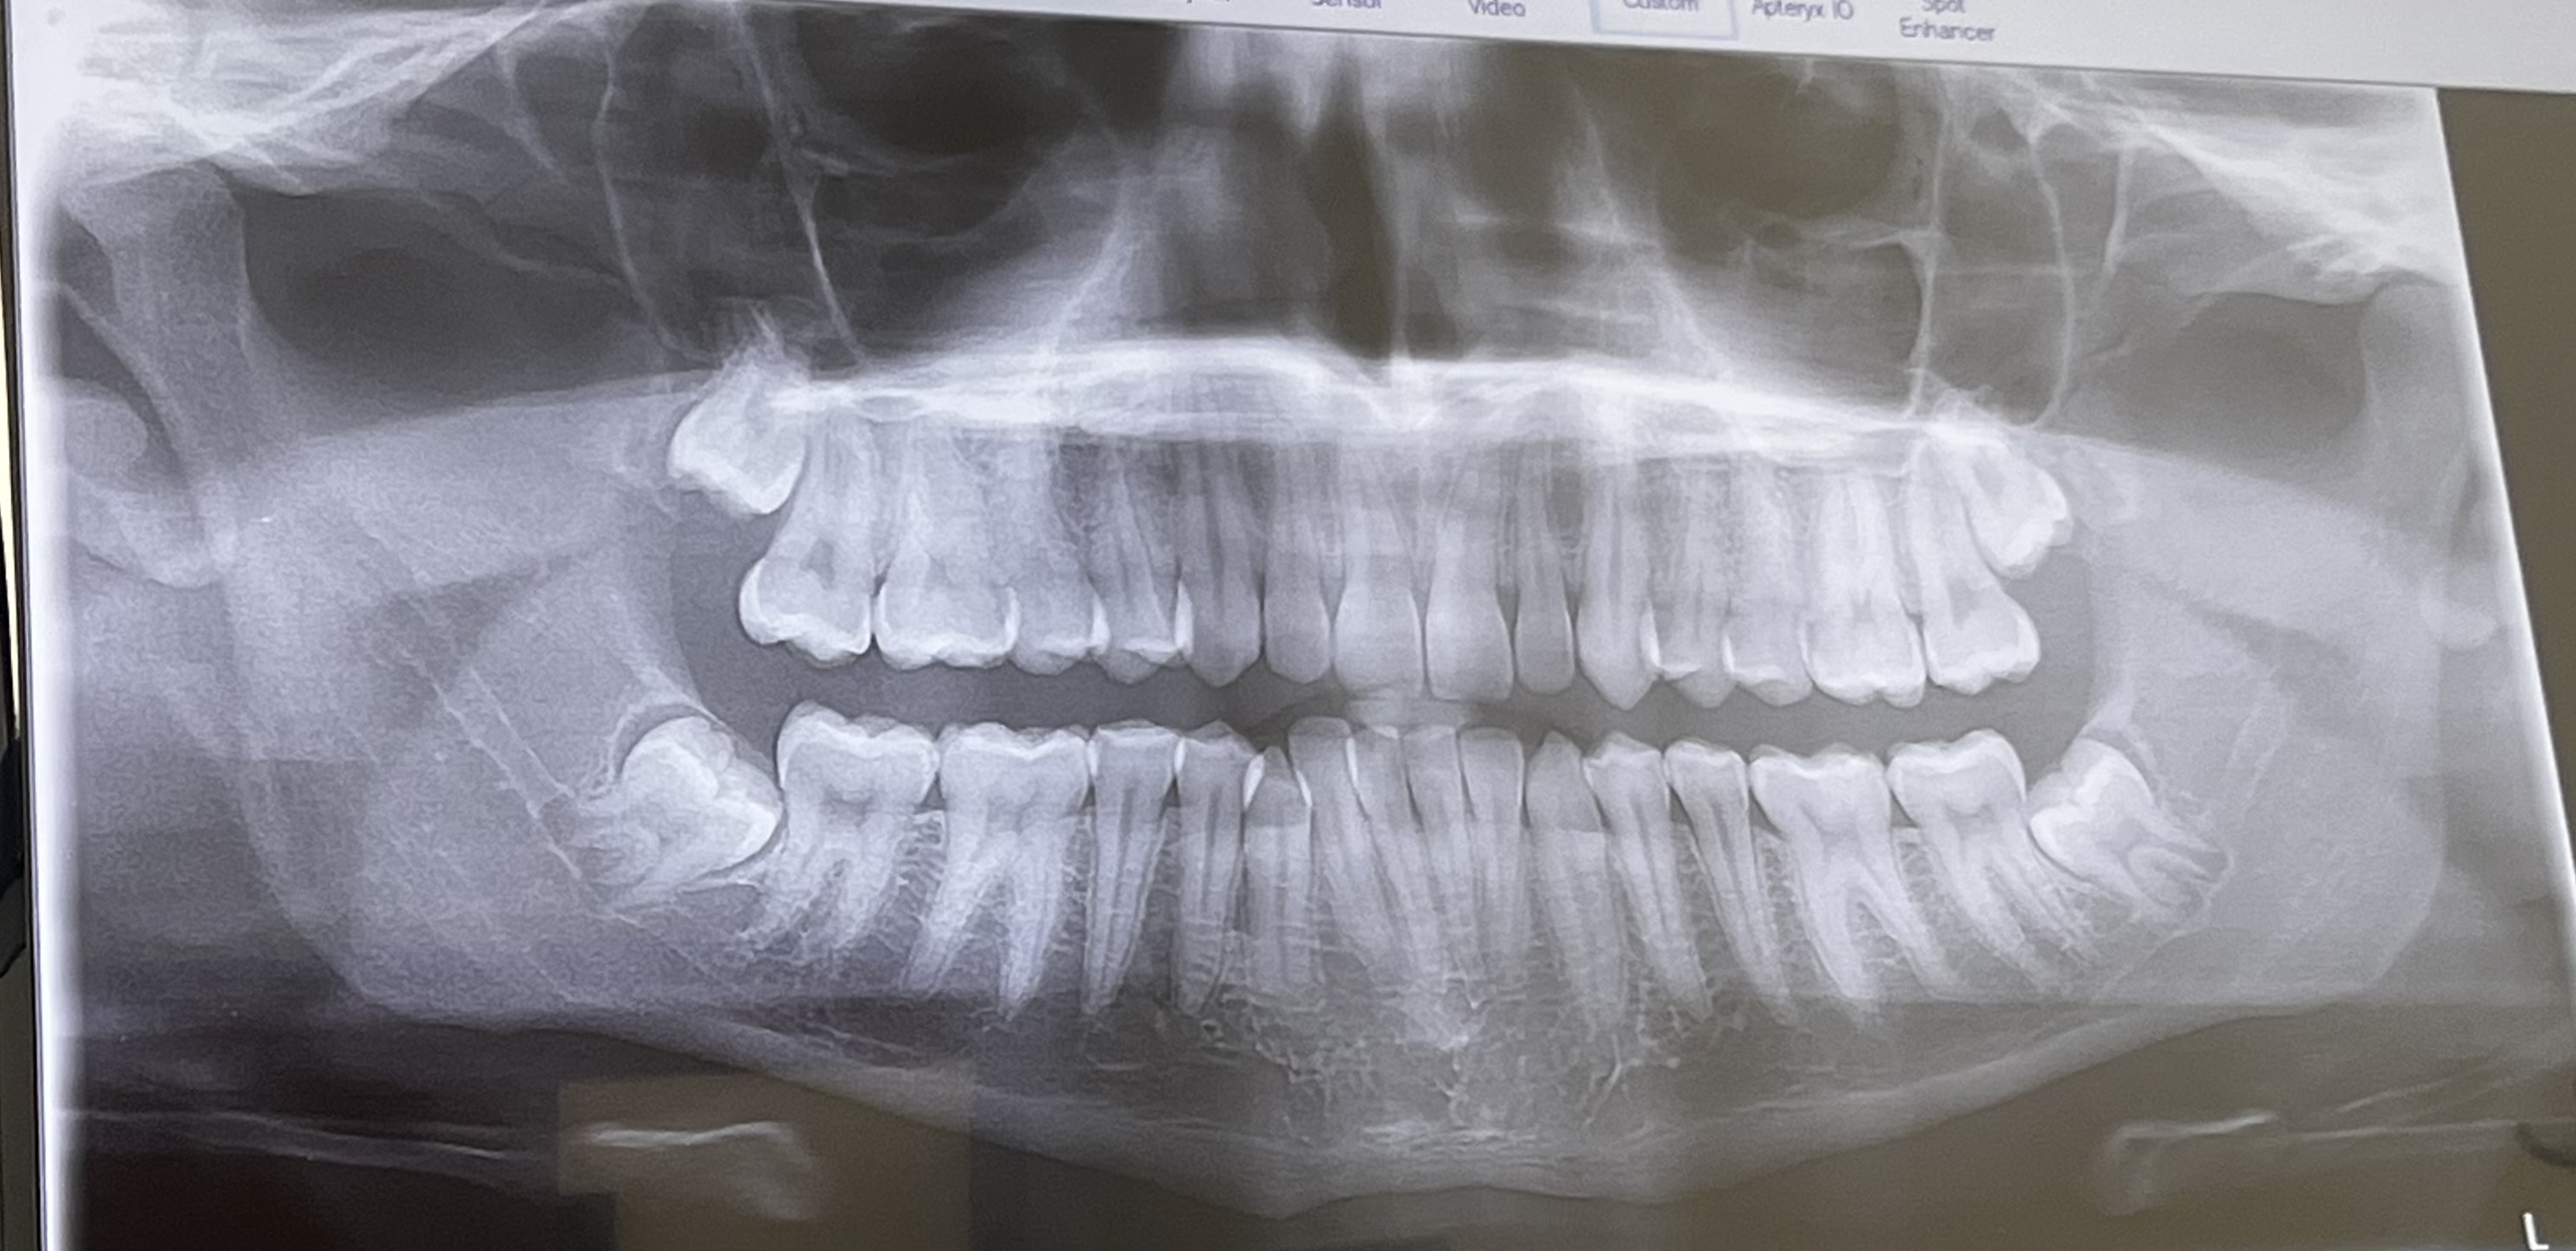

This is a pic of me JUTTING and pulling my upper lip area, trying to match my lips and see how I would possibly look after bimax (probably not accurate and not the best way to see how it would look). I also got my X-rays. Braces cost $8,000 USD. I need to Aligning my teeth and fix the lower crowded teeth the most. Ofc I’m going to start softmaxxing aswell I currently weigh like 188lbs (85kg.)